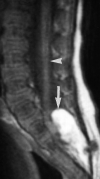

Malignant transformation of a lipomyelocele into a rhabdomyosarcoma?

We report the unusual transformation of a lipomyelocele to a rhabdomyosarcoma in a 3-year-old boy. A lipomyelocele is not considered pre-malignant, but the possibility of developing such a tumor may represent another reason for close neurological follow-up in patients with spinal dysraphism.